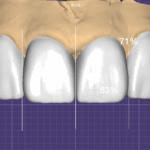

사진 8 — 라미네이트 제작

핸드메이드 빌드업 방식으로 여러 층의 세라믹을 쌓아

자연치아의 투명감과 질감을 재현.